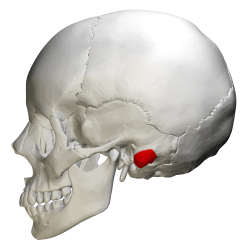

Side view of skull. Mastoid process shown in red. | |

The mastoid process is a conical prominence projecting from the undersurface of the mastoid part of the temporal bone. It is located just behind the ear canal, and lateral to the styloid process.